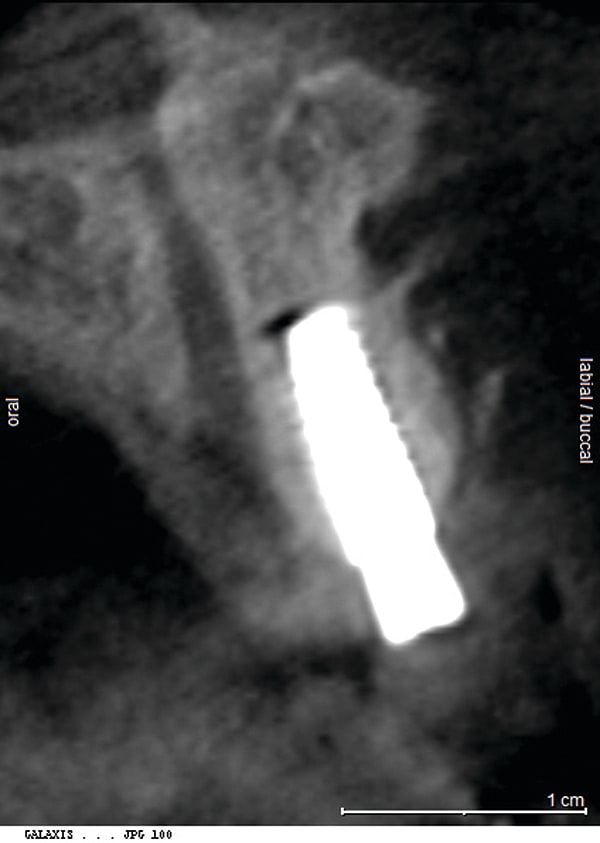

Figure 17

Figure 17 CBCT revealed 3-dimensionally sound implant placement No. 8; for optimum esthetic outcome, only a single implant for No. 8 was placed cantilevering pontic No. 7, avoiding central-lateral esthetic dilemma.